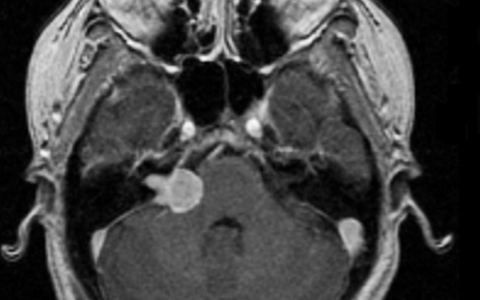

听神经瘤 (AN)又称前庭神经鞘瘤,是一种良性肿瘤,起源于前庭耳蜗神经的耳蜗部分,即八脑神经。听神经瘤少见,大约每10万人中就有1人患有听神经瘤。...

听神经瘤是脑内桥小脑角区(CPA)比较常见的脑肿瘤,中老年人多见。听神经瘤发生于前庭神经雪旺氏细胞鞘,因为面神经、听神经、前庭上和前庭下神经组...

当耳鸣患者去耳鼻喉科寻求帮助时,诊断的一步通常是听力学检查和核磁共振成像(MRI)。磁共振检查是为了排除听觉神经瘤或其他器质性耳鸣的可能性...